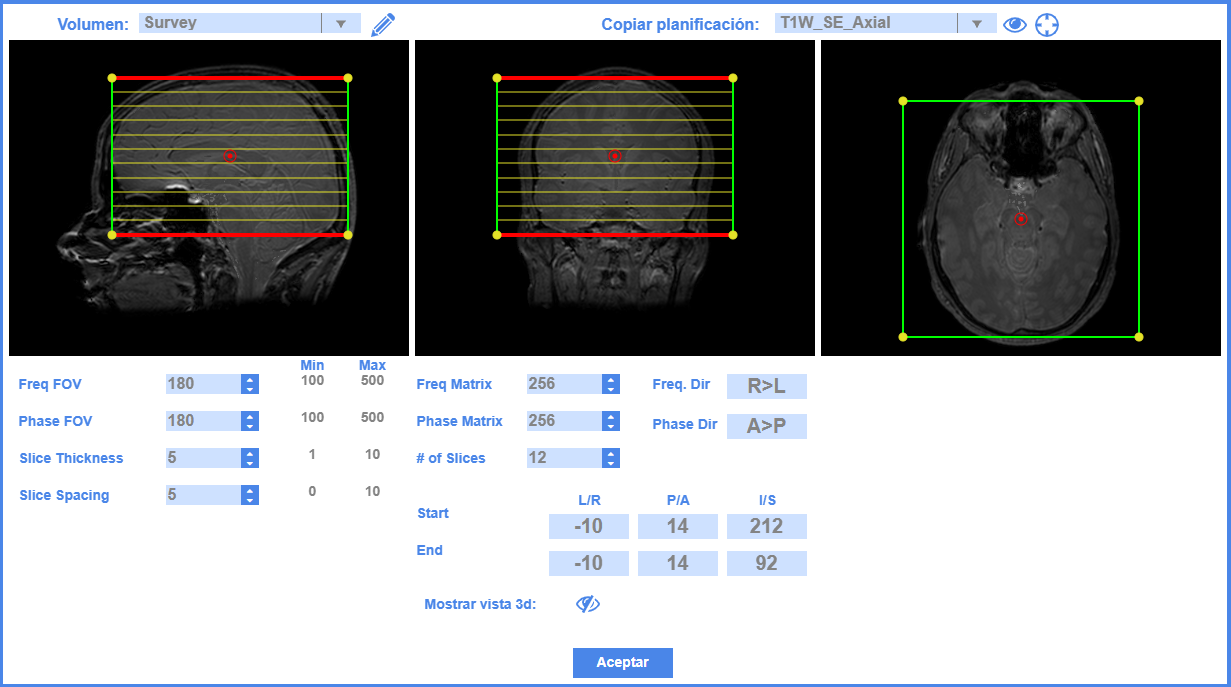

Planificación Geométrica

Ajusta con precisión la región anatómica que deseas escanear

Con herramientas intuitivas, los alumnos pueden definir las áreas de interés para la adquisición, aprendiendo la importancia de la planificación en la calidad de la imagen obtenida.